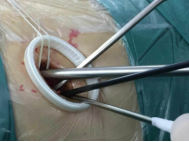

較兩孔、多孔胸腔鏡手術(shù)或傳統(tǒng)手術(shù),單孔手術(shù)具有創(chuàng)傷更小、出血更少、術(shù)后疼痛更輕、瘢痕小、切口更加美觀、術(shù)后恢復(fù)快、住院時(shí)間短等優(yōu)勢(shì)。但手術(shù)中所有器械(包括觀察鏡、吸引器、電凝鉤、切割閉合器、雙關(guān)節(jié)等各種操作器械)都要是從一個(gè)小“孔”進(jìn)入,器械之間的互相干擾,同時(shí)器械與觀察鏡幾乎平行,視野非常狹窄,手術(shù)難度明顯,增加極其考驗(yàn)醫(yī)生的技術(shù)。

器械進(jìn)入小孔。